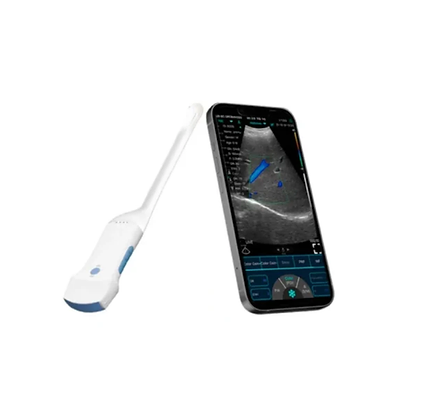

Wireless Ultrasound Machine

Wireless Ultrasound Machine

ECOLESS WIRELESS CARDIAC ULTRASOUND MACHINE

ECOLESS WIRELESS CARDIAC ULTRASOUND MACHINE

ECOLESS WIRELESS CONVEX ULTRASOUND MACHINE

ECOLESS WIRELESS CONVEX ULTRASOUND MACHINE

ECOLESS WIRELESS 3 IN 1 ULTRASOUND MACHINE

ECOLESS WIRELESS 3 IN 1 ULTRASOUND MACHINE

ECOLESS WIRELESS LINEAR ULTRASOUND MACHINE

ECOLESS WIRELESS LINEAR ULTRASOUND MACHINE

Handheld, whole-body imaging - Ultrasound

Handheld, whole-body imaging - Ultrasound